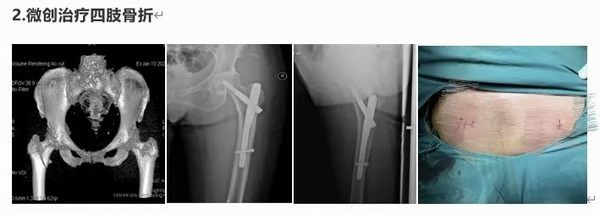

擅長四肢創傷骨折的微創修復,胸腰椎骨折復位內固定,髖關節置換術、斷指(肢)再植,拇手指再造及四肢軟組織缺損的顯微外科。